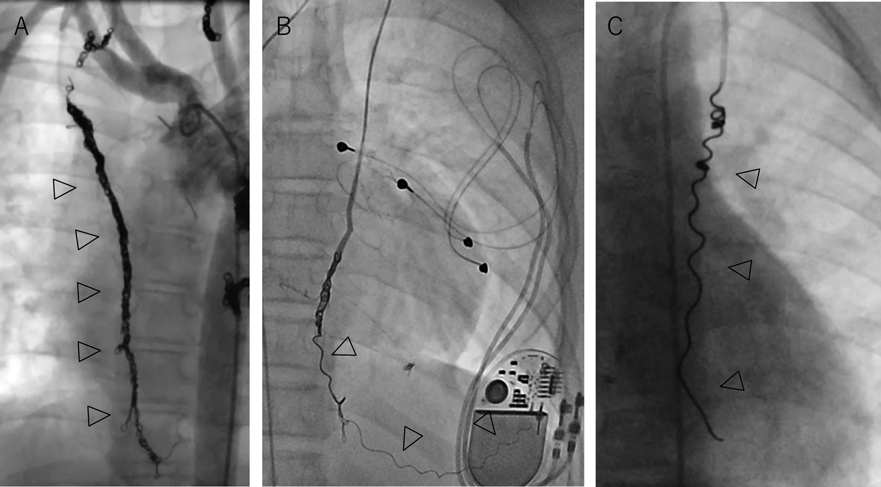

b.長い血管

Fig. 3 長い内胸動脈へのコイル塞栓

いずれもフォンタン患者における内胸動脈塞栓治療.A)長い内胸動脈を末梢からコイルを積み上げると11本のコイルが必要であった(矢頭).B)内胸動脈の末梢にAzur™18 5 mm×20 cmを巻かずにルーズに留置(矢頭).C)親カテを内胸動脈末梢まで挿入しAzur™35 4 mm×15 cmを末梢から巻かずに留置(矢頭).外膨潤型のAzur18, 35は膨潤によるコイル自体の体積増加が期待できる.